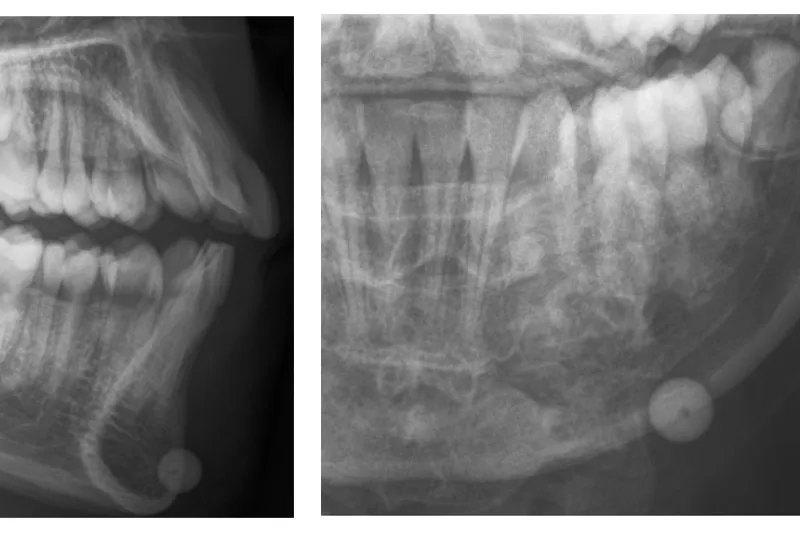

Case study – A 12-year-old boy was admitted to the Department of Oral and Maxillofacial Surgery, Aalborg University Hospital, for removal of a softgun plastic bullet in the lower lip. The injury had happened 10 days prior during play without use of safety equipment. An x-ray showed a well-defined round radiopaque foreign body located in the soft tissue near the mandibular base in region 33, 34. The bullet was removed through an intraoral approach with an non-complicated healing.

Patienttilfælde – En 12-årig dreng blev henvist til Kæbekirurgisk Afdeling, Aalborg Universitetshospital, for fjernelse af en softgun-plastikkugle i underlæben. Skudlæsionen var hændt 10 dage forinden under leg uden brug af sikkerhedsudstyr. Oversigtsrøntgen viste en velafgrænset kuglerund radiopak forandring beliggende i bløddelene nær basis mandibulae regio -3,4. Plastikkuglen blev fjernet gennem mundslimhinden i et fredeligt postoperativt forløb.